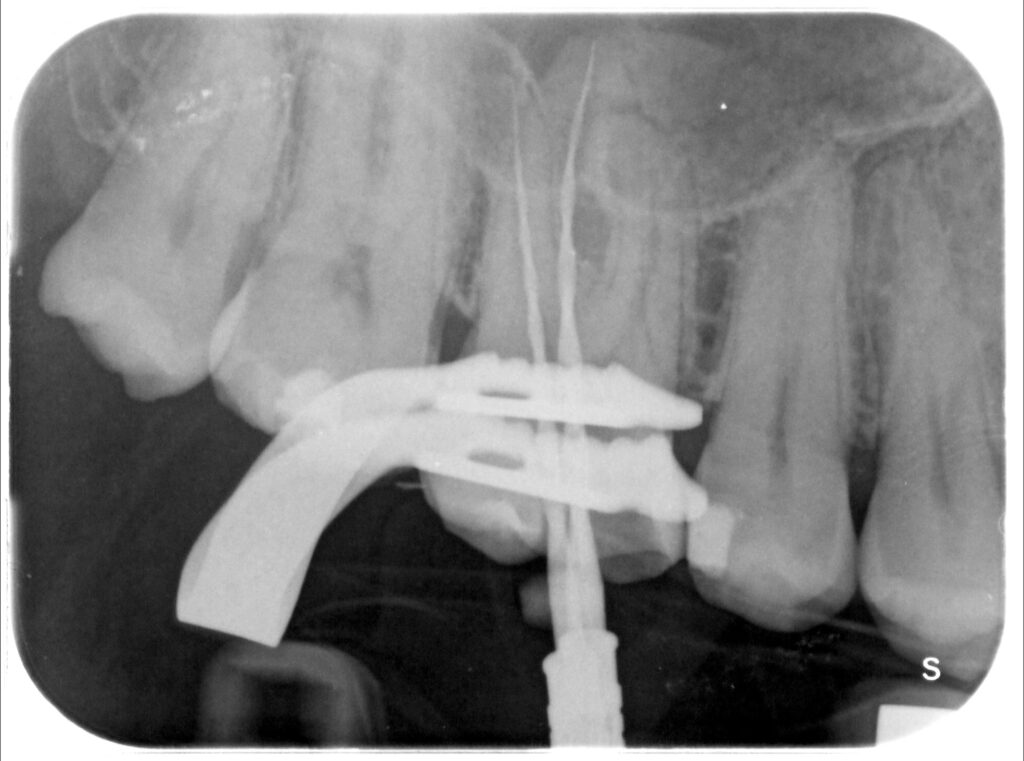

Caso clinico – trattamento ortogrado 1° molare superiore con lesione